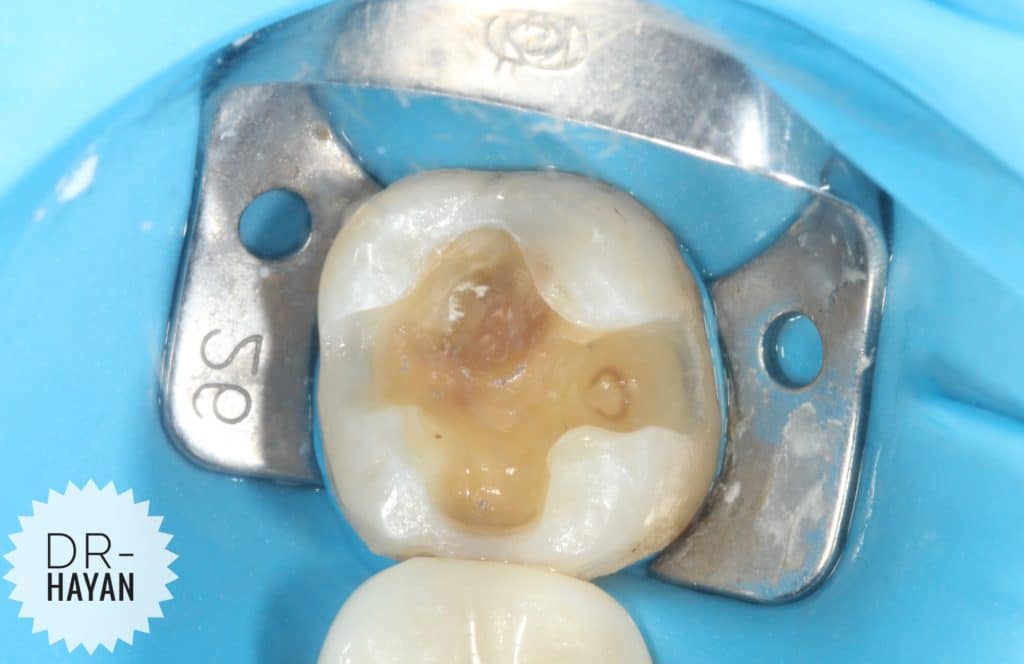

Initial view

lower 8 with Bad anatomy restoration & broken margin

With Sensitivity due to exposed dentin